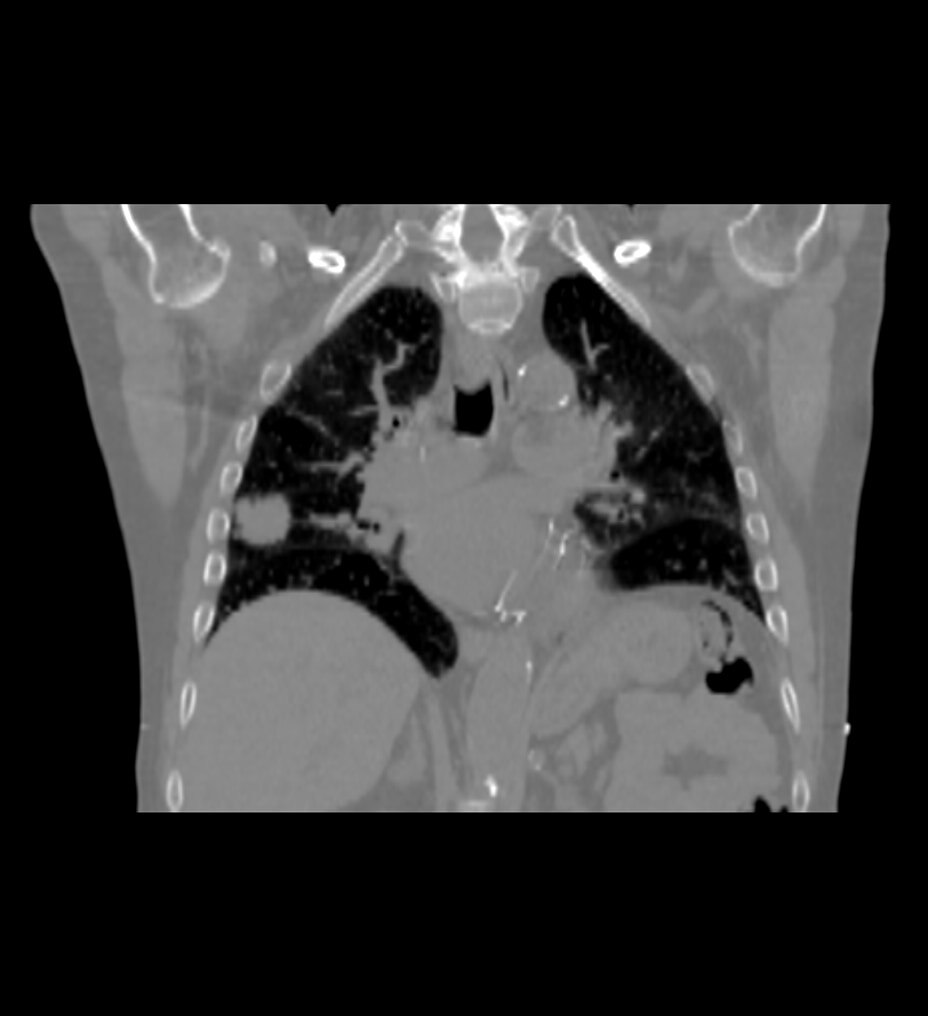

Sonic DL™ permite a los departamentos hacer lo imposible: explorar con precisión a pacientes que antes no se podían explorar de forma eficaz. Ahora, incluso los pacientes enfermos y poco colaboradores pueden someterse a exploraciones en cuestión de segundos, lo que proporciona al personal técnico tiempo libre para realizar el procedimiento con tranquilidad. Al minimizar las posibilidades de movimiento y artefactos que distorsionan las imágenes de exploración, se reduce significativamente la necesidad de volver a realizar exploraciones. Con las exploraciones de un solo latido, los pacientes ya no necesitan contener la respiración, lo que crea una experiencia de exploración más cómoda, tanto para ellos como para el personal técnico que las realiza.